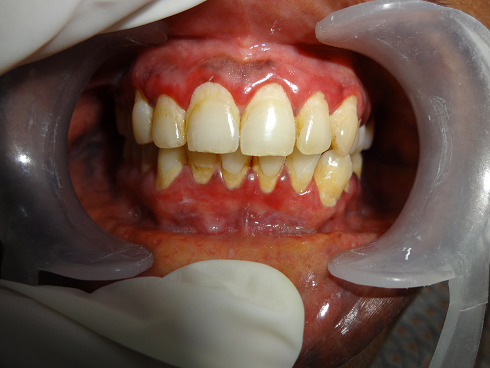

desquamative gingivitid